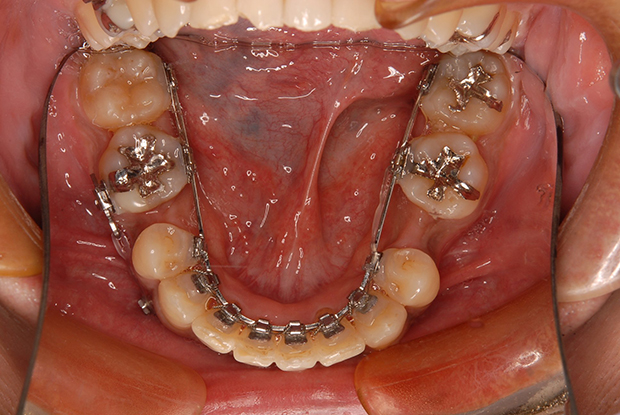

【埋伏歯】下顎前突 小児矯正 表側マルチブラケット装置

| 主訴 |

上の歯が出てこない 受け口 |

||

|---|---|---|---|

| 診断名 |

上顎左側中切歯、側切歯の埋伏歯および側切歯、犬歯の移転歯を伴う反対咬合 |

||

| 年齢 | 8歳 | 性別 | 女子 |

| 治療に用 いた装置 |

舌側弧線装置 唇側マルチブラケット装置 (メタルワイヤー) | 抜歯部位 | 非抜歯 |

| 治療期間 ・回数 |

3年10か月・46回 | 治療費 概算 |

約40万円 (調整料を含む) |

| 治療内容 詳細 |

前歯が生えてこないのをかかりつけの歯科医院にて指摘され、ご紹介された患者様です。虫歯も多い子でしたが、虫歯の治療、管理も同時に行い、小児矯正だけで綺麗に治りました。 |

||

| リスク・ 副作用 |

装置による違和感 疼痛 虫歯のリスクなど |

||